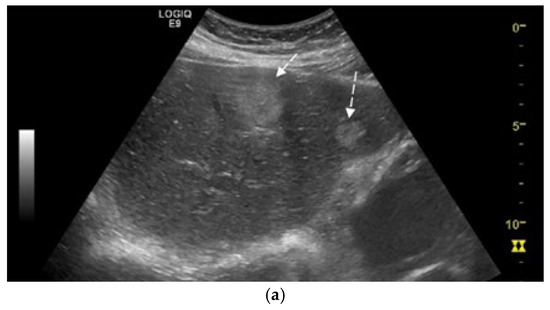

We report the case of a 67-year-old man, presented with intermittent tiredness for about three months, without associated weight loss, fever, or jaundice. The symptom was mild and episodic, occurring several times per week, and not linked to exertion or other systemic complaints. He denied abdominal pain, gastrointestinal bleeding, changes in bowel habits, cough, or flushing. From past medical history we mention chronic hepatitis C virus infection, diagnosed eight years earlier (with liver stiffness 12 kPa on transient elastography). He achieved sustained virologic response (SVR) after treatment with direct-acting antivirals (Sofosbuvir–Ledipasvir). His history also included gastric resection with gastroduodenal anastomosis for peptic ulcer disease 23 years ago, and endoscopic resection of a sessile polyp in the descending colon four years ago, confirmed as a low-grade adenomatous polyp. At the time of presentation, the patient was alert and hemodynamically stable, with vital signs within normal ranges. Physical examination revealed no jaundice, no hepatosplenomegaly, no ascites, or palpable abdominal mass, and cardiopulmonary and neurologic examinations showed no abnormalities. Laboratory investigations were within normal limits, including normal hepatic and renal function. Tumor marker levels—alpha-fetoprotein (AFP), carbohydrate antigen 19-9 (CA 19-9), and carcinoembryonic antigen (CEA)—were also within normal ranges. Abdominal ultrasound revealed three hyperechoic hepatic nodules: the largest, measuring 30 mm, in segment IVa (Figure 1a), with additional lesions in segment III (left lobe) and segment VIII (right lobe). Contrast-enhanced ultrasonography (CEUS) was performed using sulfur hexafluoride microbubbles (SonoVue®), administered as an intravenous bolus of 2.4 mL followed by a 5 mL saline flush. Arterial-phase enhancement of the hepatic nodules was observed at 10 s, with very early washout occurring at 29 s post-injection. This pattern is suggestive of malignant formations, most likely liver metastases (Figure 1b).

Figure 1.

(a) Abdominal ultrasound B-mode image capturing two hyperechoic nodules in left liver lobe (segment IVa and III) with heterogeneous, irregular contours (white arrows). (b) Abdominal ultrasound in CEUS mode at the end of the arterial phase demonstrates earlier contrast washout of both nodules compared to the rest of the liver parenchyma (white arrows).